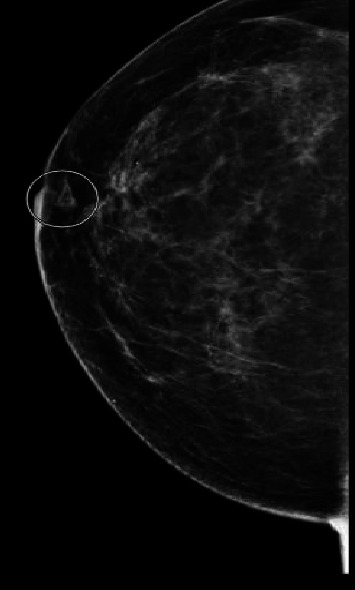

Granulomatous mastitis (GM) is a rare inflammatory condition of the breast that can mimic inflammatory breast cancer. We report a case of a 54-year-old female who developed recurrent GM symptoms in the context of drug-induced hyperprolactinemia, which resolved with dopamine agonist therapy. Our report suggests that serum prolactin should be tested in patients with GM and appropriately managed if elevated.

Abstract Image